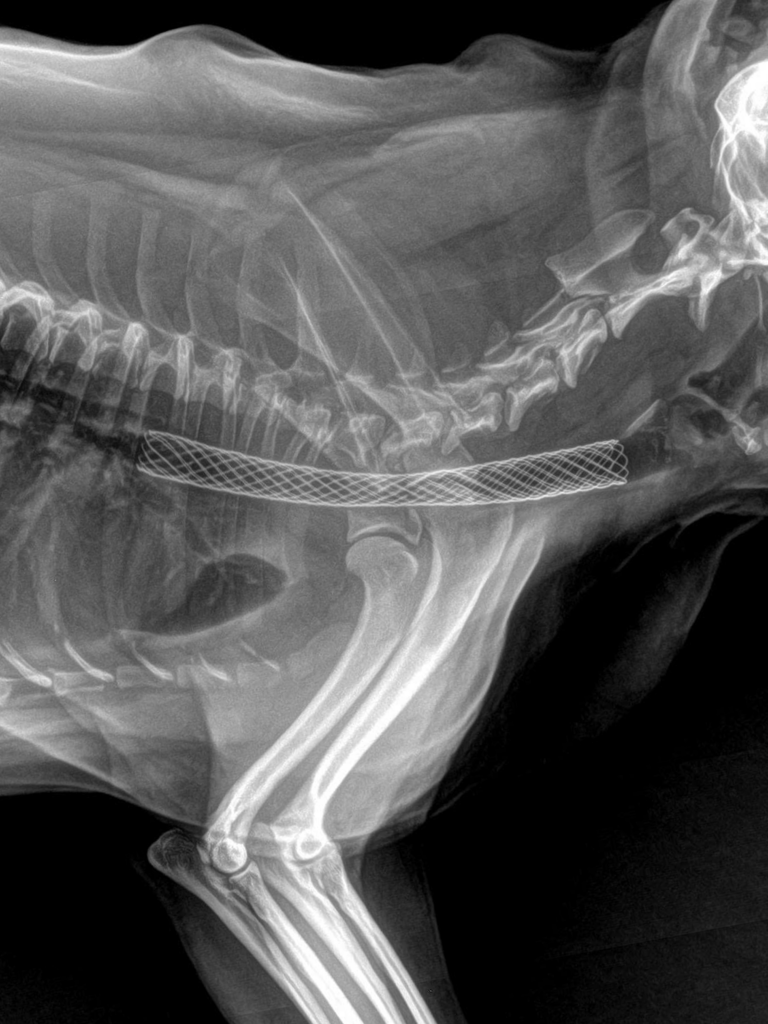

2.2. Đánh giá khoang ngực và hệ hô hấp

Phim X-quang kỹ thuật số cung cấp cái nhìn tổng quan về tình trạng lồng ngực. Bác sĩ có thể quan sát bóng tim để phát hiện dấu hiệu suy tim lớn, kiểm tra cấu trúc phế quản, phổi để chẩn đoán các bệnh lý như viêm phổi, tích dịch màng phổi hay tổn thương do chấn thương ngực.